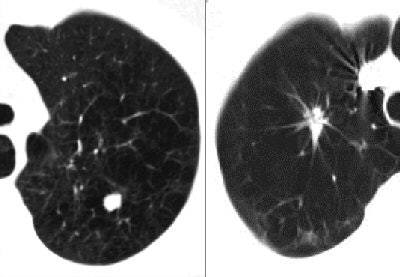

![]() |

| The benign-appearing nodule on the left is malignant; the spiculated mass on the right is benign. All images courtesy of Dr. Ella Kazerooni. |